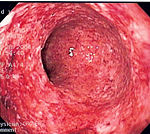

Endoscopy

A colonoscopy is the best test for making the diagnosis of Crohn's disease as it allows direct visualization of the colon and the terminal ileum, identifying the pattern of disease involvement. Occasionally, the colonoscope can travel past the terminal ileum but it varies from patient to patient. During the procedure, the gastroenterologist can also perform a biopsy, taking small samples of tissue for laboratory analysis which may help confirm a diagnosis. As 30% of Crohn's disease involves only the ileum, cannulation of the terminal ileum is required in making the diagnosis. Finding a patchy distribution of disease, with involvement of the colon or ileum but not the rectum, is suggestive of Crohn's disease, as are other endoscopic stigmata.The utility of capsule endoscopy for this, however, is still uncertain.